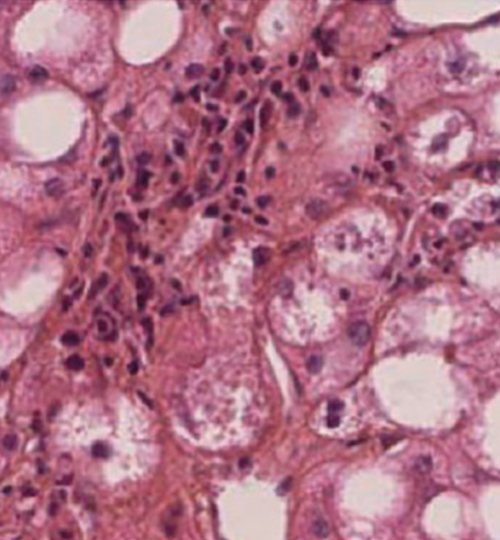

La stéatose hépatique (image) associe un infiltrat inflammatoire à polynucléaires neutrophiles et des lésions hépatocytaires (ballonnisation, nécrose et corps de Mallory). Ce sont les mêmes lésions que celles observées lors d'une hépatique alcoolique, étiologie à exclure. Crédit image : Catherine Guettier.